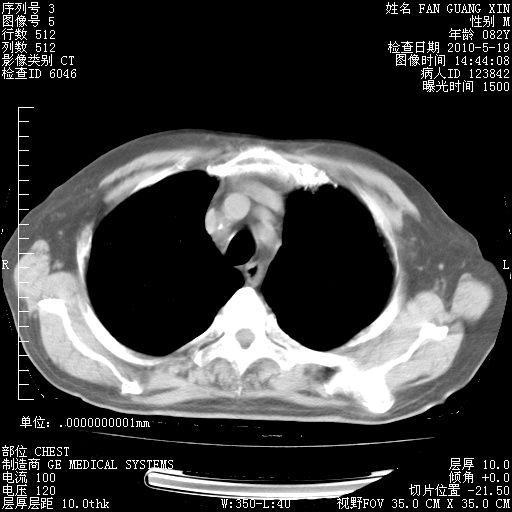

复查肺部CT,明显好转。为什么发热呢?

治疗3周后的肺部CT

治疗3周后的肺部CT纵隔窗